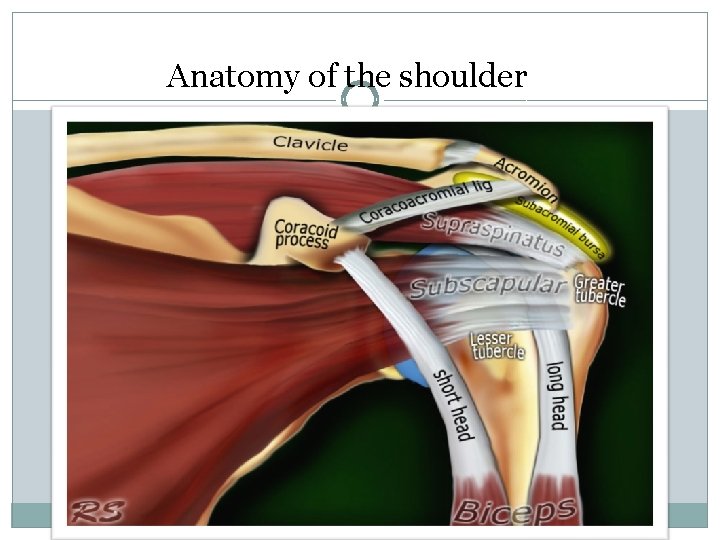

Anatomy of the shoulder

Anatomy of the shoulder

shoulder joint is the most mobile joint of the body Joints The shoulder consists of three joints: 1 -Acromioclavicular 2 -Sternoclavicular 3 -Glenohumeral joint And two gliding planes: 1 -Scapulothoracic 2 -Suacromial

Anatomy of the shoulder

Anatomy of the shoulder